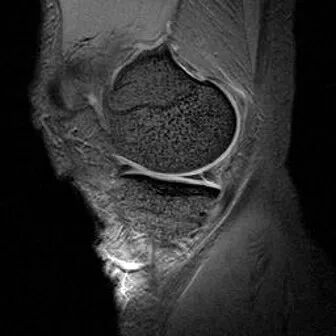

1、宽度减小,在通过半月板体部的冠状面上蝶形消失,同时可见内移的半月板位于髁间窝、交叉韧带旁2、矢状面示残余的前角或后角变小或截断3、半月板前(后)角增宽或双半月板前(后)角征4、双前交叉韧带或双后交叉韧带征

桶柄状撕裂:宽度减小,在通过半月板体部的冠状面上蝶形消失,同时可见内移的半月板位于髁间窝、交叉韧带旁

桶柄状撕裂:半月板后角增宽